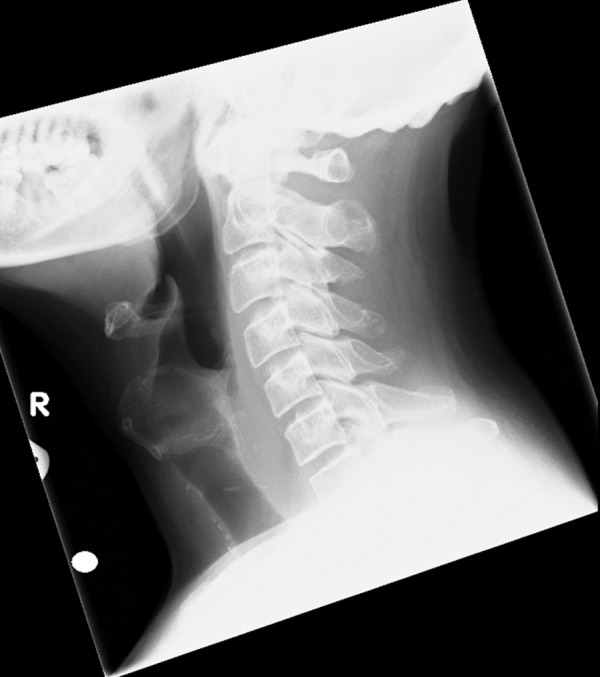

Figure 3.

Lateral soft tissue neck X-ray.

The soft tissue neck X-ray (figure 3) did not show any retained radio-opaque foreign body. The ultrasound scan (USS) of his neck revealed a 21 mm×18 mm×31 mm well-defined hypoechoic area within the right-sided strap muscles indenting the superior border of the right lobe of the thyroid gland. Overall, the appearances were consistent with a resolving infection or haematoma (figure 4). A fine-needle aspiration yielded 2 mL of frank pus. The cytological examination showed a cellular specimen and consisted of neutrophil polymorphs. The features were in keeping with an acute inflammatory process, an abscess. The microscopy of the aspirated material revealed Pus cells +++ and Gram-positive cocci ++ but no acid and alcohol fast bacilli were observed on tuberculosis (TB) microscopy. On culture, a profuse growth of Streptococcus milleri was established sensitive to clindamycin, doxycycline, erythromycin, penicillin and tetracycline. There was no growth in 12 weeks on a mycobacterial culture.